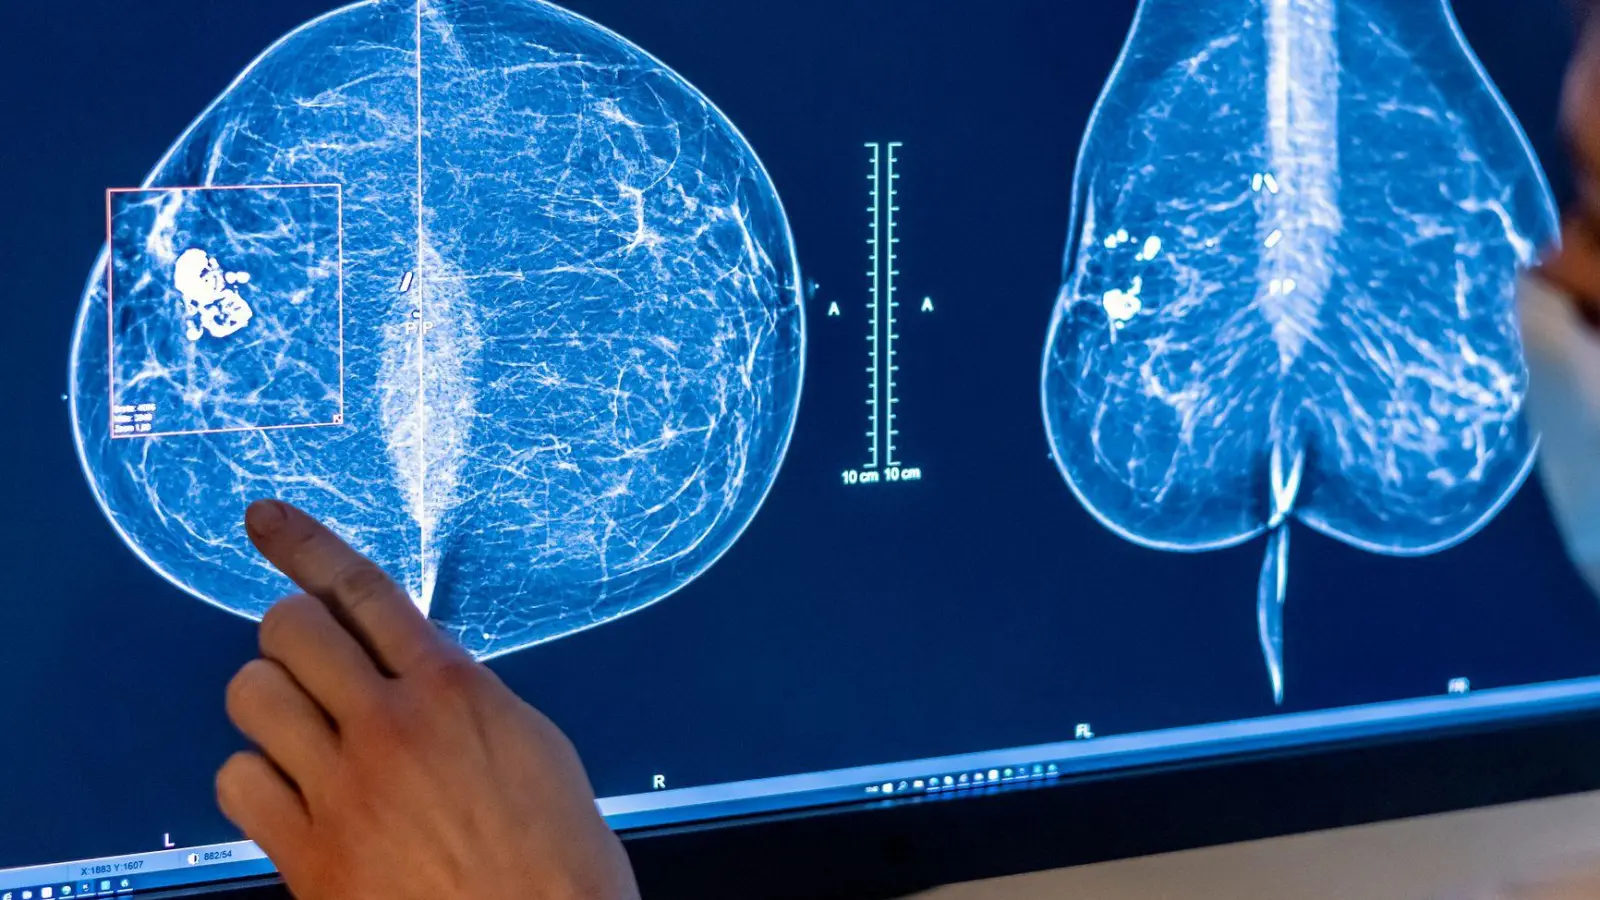

2023 wurden rund eine halbe Million Menschen in Deutschland mit Krebs diagnostiziert. (Symbolbild) (Foto: Hannibal Hanschke/dpa)

Im Jahr 2023 wurden demnach bei rund einer halben Million Menschen in Deutschland eine Tumorerkrankung neu diagnostiziert. Von diesen 517.800 Krebserkrankungen traten rund 276.400 bei Männern und etwa 241.400 bei Frauen auf. Etwa die Hälfte aller Neuerkrankungen betrafen die Prostata (79.600), die Brustdrüse (75.900), die Lunge (58.300) oder den Dick- und Enddarm (55.300).